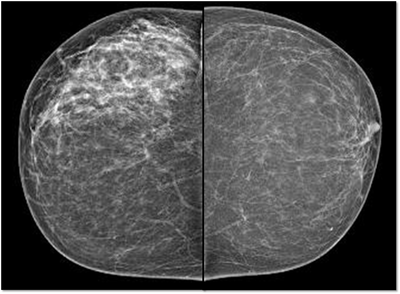

MG: Right breast shows focal asymmetric density in lateral quadrant extending for an area of 12.4 x 6.5 cm with no associated discrete mass or suspicious calcifications. Correlative ultrasound showed a heterogeneous area with echogenic vascular surrounding parenchyma in lateral quadrant with no discrete solid masses. MRI breast was performed on day 14 of LMP. Right breast shows an area predominantly consisting of fat in lateral quadrant extending for an area of 1.2×5.5x 8.9 cm along its maximum AP, ML and CC dimensions. This area is bright on fat suppressed T2 sequences and shows significant restriction on diffusion weighted sequences. There is rapid and progressive non mass enhancement in the above area extending anteriorly in to the nipple and posteriorly into the pectoralis major muscle. Two large and tortuous feeding vessels are seen to arise from the subclavian and axillary arteries respectively. Right breast shows predominantly fat containing mass showing abnormal enhancement described. The possibilities include vascular neoplasm or remotely fat necrosis. Ultrasound guided core biopsy was Suggestive of an inflammatory lesion, possibly fat necrosis. However enlarged and tortuous feeding arteries to the vascular mass was worrisome and we recommended an excision biopsy correlation. Excision biopsy showed “Multiple patchy areas of dense inflammatory infiltration in a background of fat necrosis”.